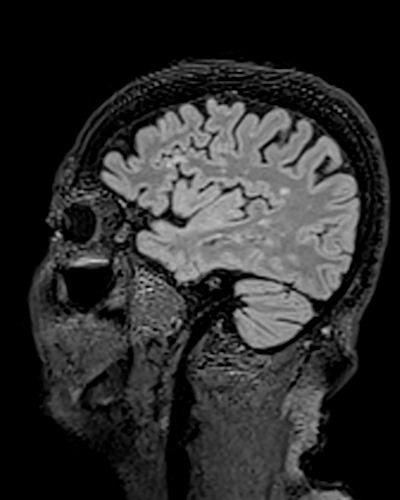

Mark the MS characteristic lesion